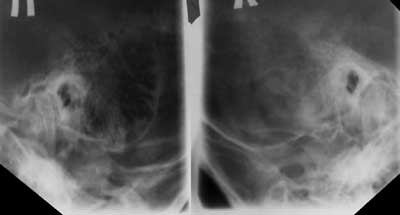

Рис. 3а. Латентный мастоидит. В проекции Шуллера затемнены клетки сосцевидного отростка, разрушены межклеточные перегородки слева.